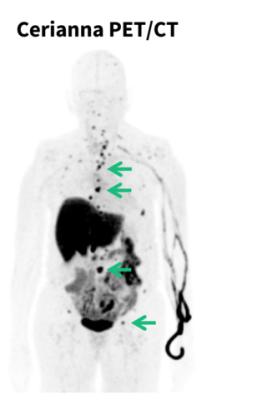

Cerianna is a molecular imaging agent indicated for use with PET imaging for the detection of ER+ lesions as an adjunct to biopsy in patients with known or suspected recurrent or metastatic breast cancer. Cerianna works by binding to functional ER lesions and then the whole body is imaged by PET scan to help doctors assess and treat lobular breast cancer appropriately. With its diffuse growth patterns, detection and biopsy of ILC can be more difficult. Cerianna provides an alternative method to assess ER status across the whole body.

Lobular tumors typically do not form lumps which makes the cancer harder to detect with self-exams, mammography, ultrasound and magnetic resonance imaging (MRI). ILC can also recur more than a decade[v] after initial diagnosis and metastasize to unusual places such as the bones, brain, liver, lungs, gynecological organs, and others.[vi][vii] Once recurrent or metastatic lobular breast cancer is suspected, the new guidelines recommend considering FES PET imaging of the whole body to assess whether ER+ lobular tumors are present.